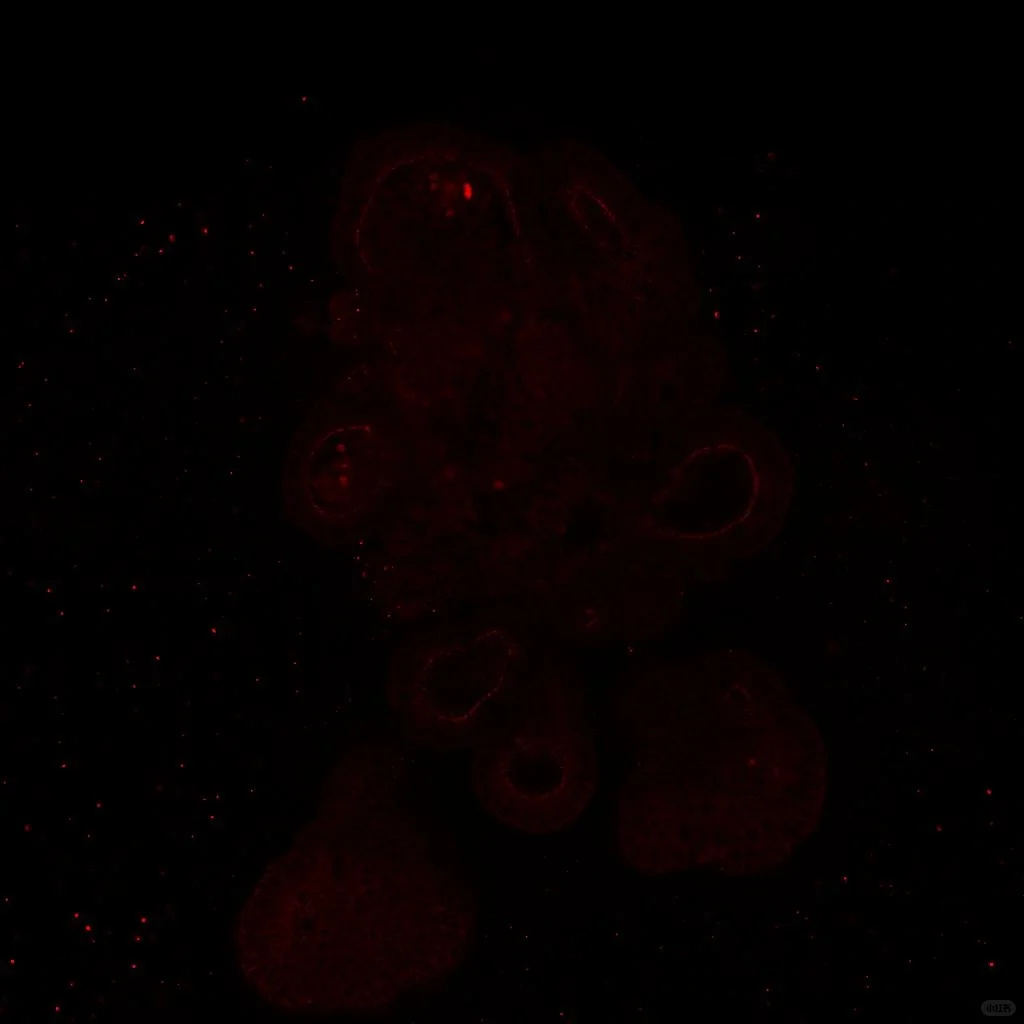

小鼠小肠类器官免疫荧光(共聚焦拍摄)

太好看了!!!染了紧密连接蛋白、干性指标以及LYSM,相对于传统的切片染色,共聚焦拍摄下的结构更立体且完整。